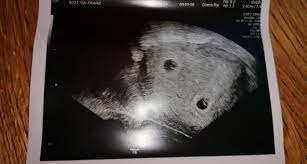

Ab wann kann man im ultraschall erkennen, ob man eineiige oder zweieiige zwillinge bekommt? Kann man von dem auch iwelsche hilfe gebrauchen/beantragen? Hallo ich würde gerne wissen ab wann man beim ultraschall erkennen kann ob es zwillinge werden und ob es vorher schon zu erkennen ist z.b wenn sich keins versteckt kann man es sehen sobald man die fruchthöhle sieht (oder eben dann zwei) oder wenn man eine/zwei embyonalanlagen sieht. Hallo 8baby8, in der 8.ssw (7+2) könnte man eine zweite fruchthöhle erkennen. Für die meisten frauen, die keine fruchtbarkeitsbehandlung hatten.

Bei einer kinderwunschbehandlung kannst du davon ausgehen, dass deine babys zweieiig sind. Wann kann man kindergeld, elterngeld beantragen? Wann kann man per ultraschall das geschlecht erkennen? Im ultraschall kann man meist auch sehr gut erkennen, ob es sich um eineiige (monozygote) oder zweieiige (dizygote) zwillinge handelt. Innerhalb des ersten schwangerschaftsdrittels stellt sich heraus, ob sie zwei während einer ultraschalluntersuchung kann der arzt oder die ärztin schon erkennen, ob es sich um eineiige oder zweieiige zwillinge handelt. Kann ich dabei das geschlecht meines kindes erfahren? Man erkennt zwillinge schon, sobald die herzaktionen im ultraschall erkennbar sind. Um eine übersicht über solche themen sowie wichtige. Für die meisten frauen, die keine fruchtbarkeitsbehandlung hatten. Behandelt man zwillinge anders als andere geschwister? Ab wann kann man die arbeit mit jungen pferden beginnen? Ich würde mir eine 2. Wann kann man schwanger werden?

Im ultraschall kann man meist auch sehr gut erkennen, ob es sich um eineiige (monozygote) oder zweieiige (dizygote) zwillinge handelt.